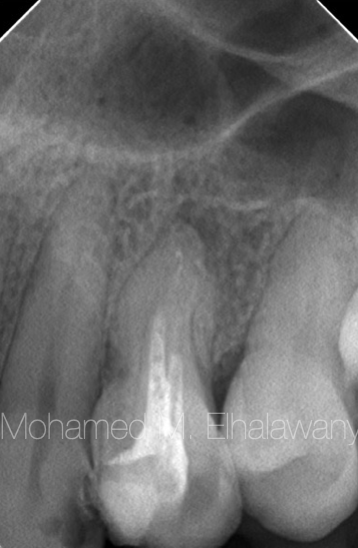

图1

一名39岁的患者因无痛的牙龈肿胀而迅速就诊,担心可能患有恶性肿瘤。在检查过程中,牙医告诉她,她患有一个从腐烂的第一前磨牙(编号24)的根尖区域延伸到骨外的脓肿,形成牙龈肿胀,因此需要对该前磨牙进行根管治疗,并对肿胀进行切开和引流(根据患者的描述)。

经过近七个月的持续治疗后,患者的牙医将此病例转诊到我的诊所,以寻找解决这个不愈合肿胀的方法,尽管根管已经干燥,且对肿胀进行了手术切开(如图1所示),但仍未见效,并且在脓肿内使用了抗生素也未见效。

注意:当询问患者牙医在这七个月期间拍摄的X光片以审查治疗过程中的进展时,惊讶的是,医生认为没有必要拍摄X光片,因为在他看来,这只是一个直接由于牙齿腐烂而引起的脓肿案例。

术前根尖X光片显示牙齿根管内填充了未知物质,但奇怪的是,这个肿胀并没有在X光片上显现,只是在牙周膜上有轻微的扩张。根据这些情况,需要进行更多的放射学检查,从各个方向检查该前磨牙及其周围结构,以确定囊肿的原因以及为何在X光片上未显示。因此,要求进行术前锥形束CT(CBCT)检查。